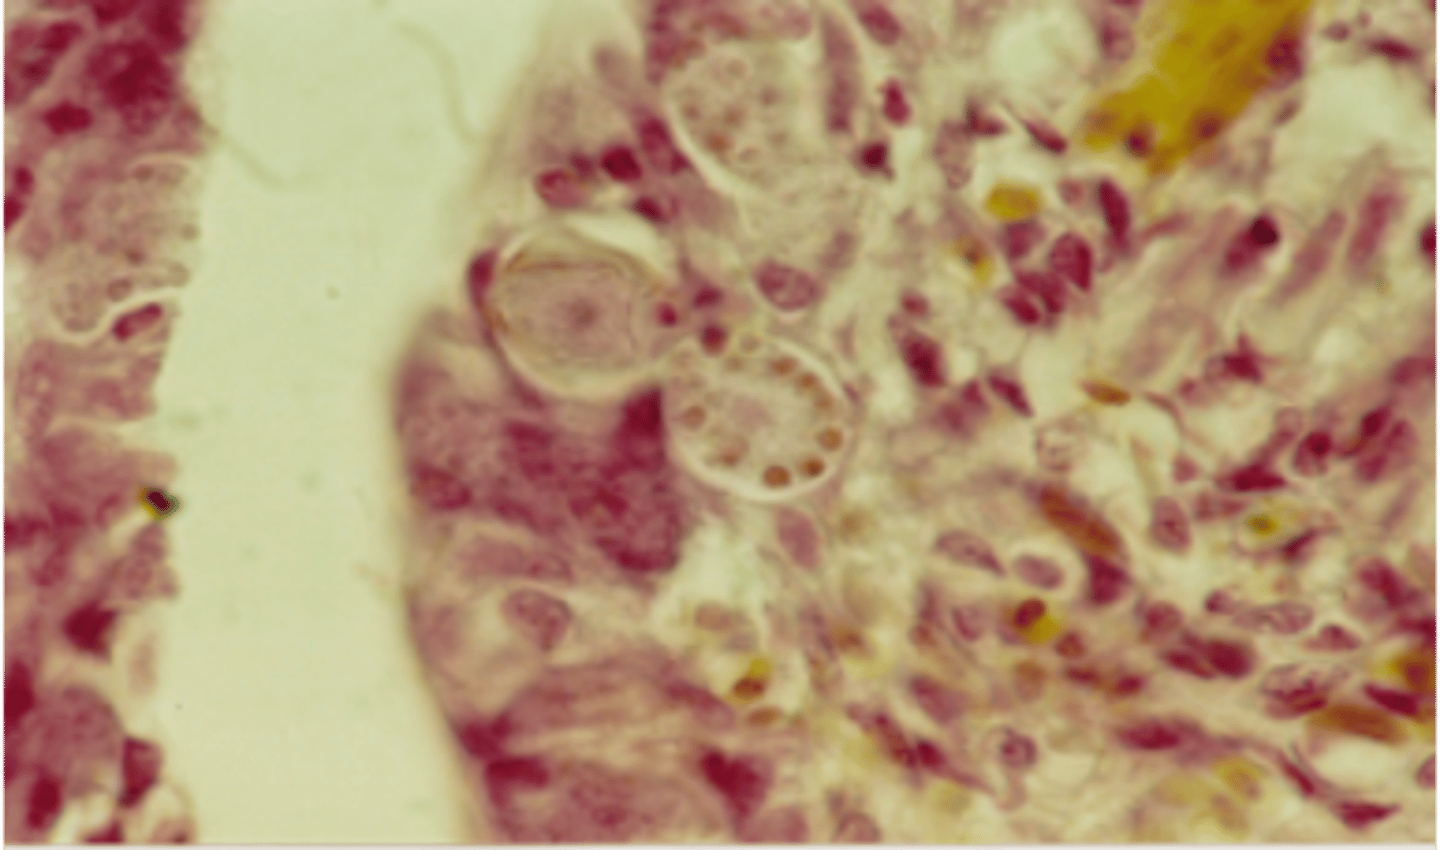

Slide from a dead chicken - What parasite and life stage is this?

Eimeria spp. - Merozoites (banana-shaped, central red nuclei)

Eimeria spp. - Microgametocyte (see many small microgamonts within cell)

Eimeria spp. - Schizonts (many merozoites within them)

Eimeria spp. - Macrogametocyte (see wall forming bodies)

Eimeria spp. - Sporulated oocyst (20 microns).